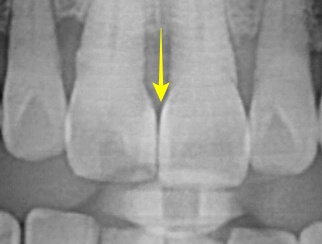

남성분의 입안 상태는 위와 같습니다.

사진을 보시면 대문니 오른쪽 대문니가(사진상으로는 왼쪽) 틀어져 있는 것을 볼 수가 있었습니다.

오른쪽 사진의 노란색 화살표를 보시면 레진과 치아 사이에 턱진 곳이 없으며 부드럽게 이행되는 모습을 볼 수 있습니다.